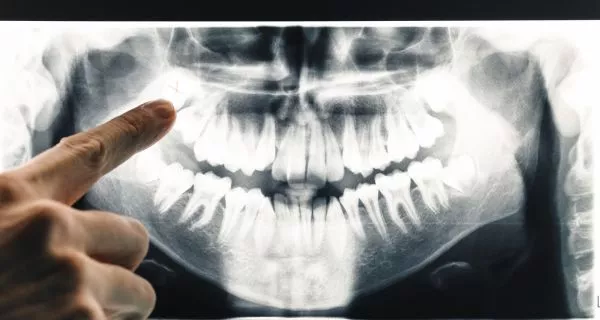

Antes de entender por qué existe el agujero, es útil saber como se hace la extracción. Hay dos tipos principales, y el que te corresponde depende de como esta tu muela.

Se necesita cuando la muela del juicio está debajo de la encía, creciendo en un ángulo incorrecto, o sólo parcialmente visible. A esto se le llama muela impactada.

- El cirujano o dentista hace un corte pequeño en la encía, a veces retira un pedazo mínimo de hueso y puede dividir la muela en partes para sacarla con seguridad.

- Este tipo de extracción deja una herida más grande y tarda más en sanar, lo cual es completamente normal.